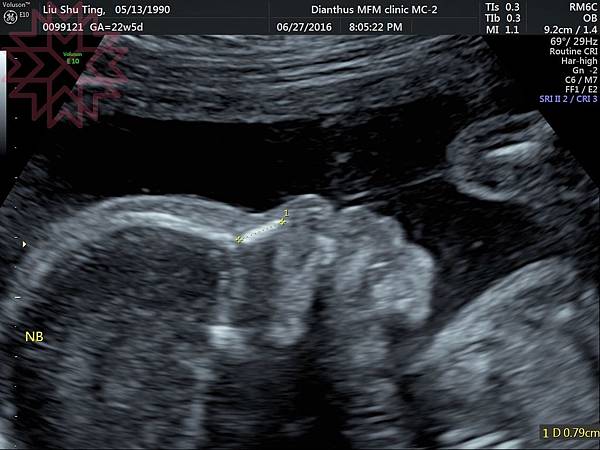

這就是讓我們數的很辛苦的腳ㄚ子~